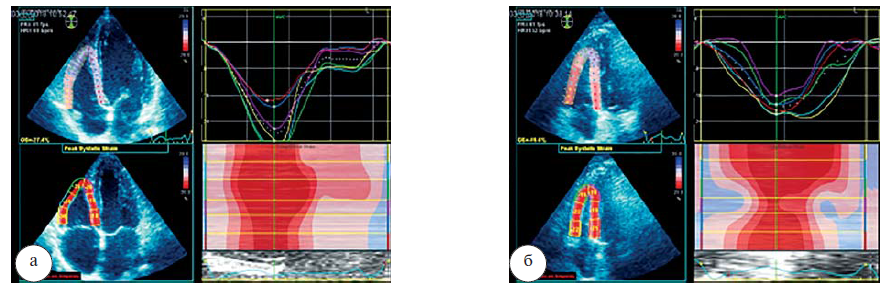

ФВ ПЖ в 3D-режиме, как и КДО и КСО ПЖ в покое в группах статистически не различалась, и её значения были в пределах нормы, представленной в рекомендациях ASE/EACVI (2015), т. е. ФВ ПЖ составляла не менее 45% (рис 1).

Рис. 1. Результаты ЭхоКГ здорового мужчины 35 лет в покое (а): ФВ ПЖ в 3D-режиме=55,4%; пациента К. 35 лет, страдающего саркоидозом легких II стадии, в покое (б): ФВ ПЖ в 3D-режиме=52,1%

Исходя из полученных результатов, очевидно, что глобальная продольная деформация ПЖ в КГ и ОГ как в покое, так и на фоне ФН находятся в пределах нормальных значений (> –20%) согласно ASE/EACVI, 2015. В состоянии покоя статистических различий по данному показателю между группами не выявлено (р=0,27). Показатели GLS ПЖ у пациентов, страдающих саркоидозом, на фоне нагрузки снижаются (табл. 2; рис. 2,3) в отличие от здоровых лиц, у которых отмечается увеличение глобальной продольной деформации ПЖ (от –24,1±2,7 до –25,1±3; р=0,002). Важным является тот факт, что, несмотря на отсутствие различий в группах по GLS ПЖ в покое, на высоте нагрузки отмечается статистически значимое снижение GLS ПЖ у пациентов, страдающих саркоидозом легких (р=0,00001).